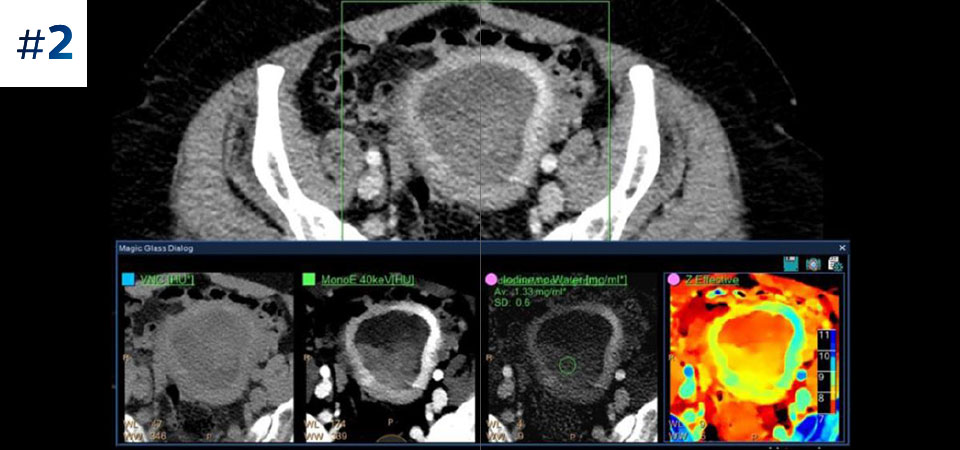

Go beyond conventional CT. See how layers of spectral-detector results can enhance your diagnostic confidence.

See the difference between spectral-detector CT and conventional CT